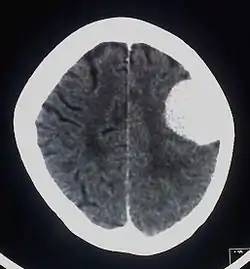

Meningeom

Et meningeom er en lokal fortykkelse af hjernehinden.

Meningeomer udgår fra hjernens hinder og kan derfor sidde alle de steder, hvor der er hinder i hjernen. Meningeomer sidder uden på hjernen og trykker på hjernen, fordi kraniet ikke kan give sig. De kan langsomt vokse ind i kraniets knogler og eventuelt også gennem kraniet.